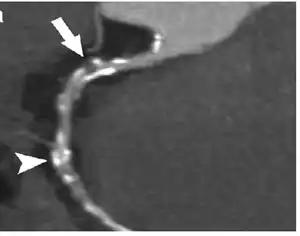

Predominantly noncalcified plaque with high-grade stenosis of LAD[2]

2. Eckert, Joachim; Schmidt, Marco; Magedanz, Annett; Voigtländer, Thomas; Schmermund, Axel (February 2015). "Coronary CT Angiography in Managing Atherosclerosis". International Journal of Molecular Sciences. 16 (2): 3740–3756. doi:10.3390/ijms16023740. ISSN 1422-0067.{{cite journal}}: CS1 maint: unflagged free DOI (link)